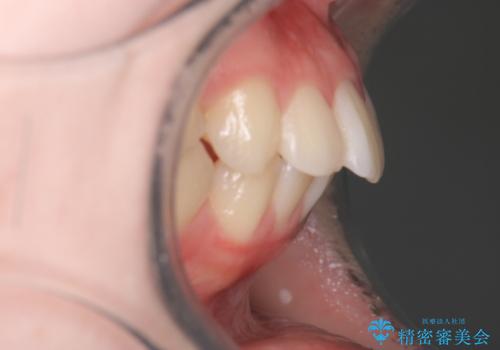

【審美装置】歯を抜いてEラインをきれいに

- 出っ歯を主訴に来院されました。今回は4番の歯を4本抜歯をし、ワイヤー矯正にて治療しました。

抜歯矯正のため2年を予定してましたが、予定よりも早く終わることができました。また口元も下がり、かみ合わせも改善しました。